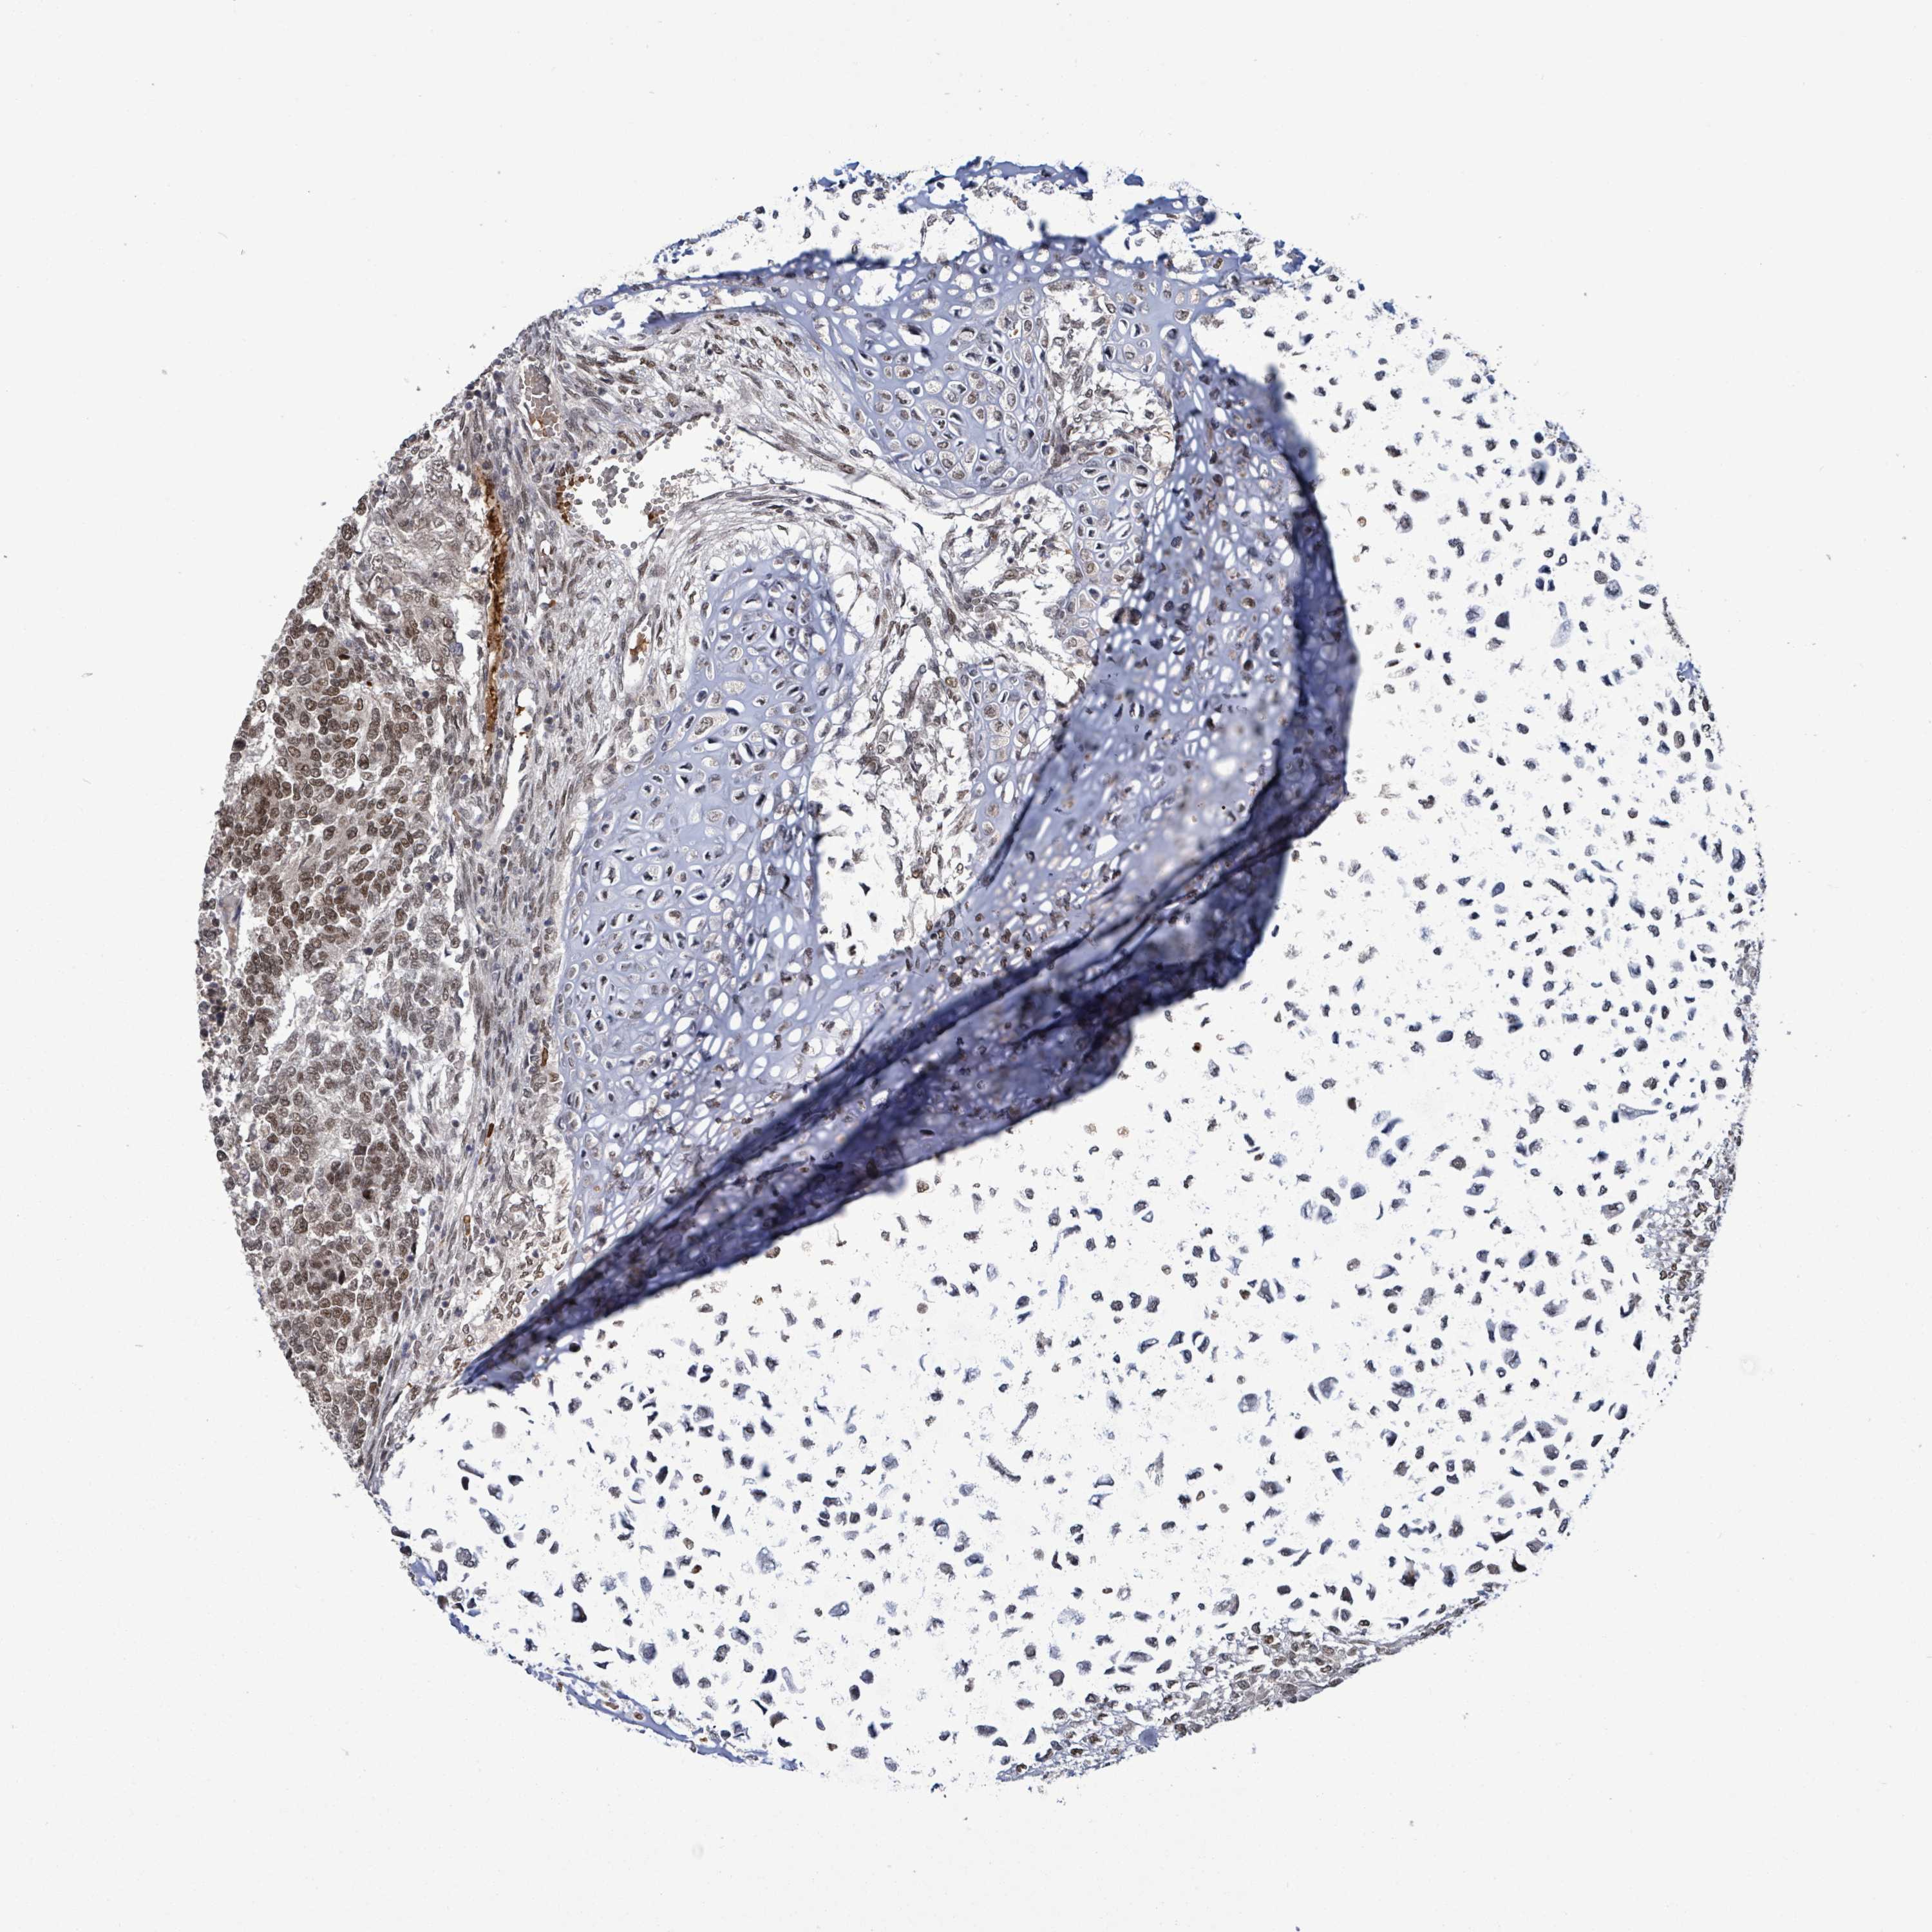

TESTIS CANCER - Protein expressioni

A mouse-over function shows sample information and annotation data. Click on an image to view it in a full screen mode. Samples can be filtered based on level of antibody staining by selecting one or several of the following categories: high, medium, low and not detected. The assay and annotation is described here.

Note that samples used for immunohistochemistry by the Human Protein Atlas do not correspond to samples in the TCGA dataset.

Antibody stainingi

Antibody staining in the annotated cell types in the current human tissue is reported as not detected, low, medium, or high, based on conventional immunohistochemistry profiling in selected tissues. This score is based on the combination of the staining intensity and fraction of stained cells.

Each image is clickable and will lead to virtual microscopy that enables deeper exploration of all samples and also displays staining intensity scores, fraction scores and subcellular localization as well as patient and tissue information for each sample.

Antibody HPA048315

Seminoma, NOS

Carcinoma, Embryonal, NOS